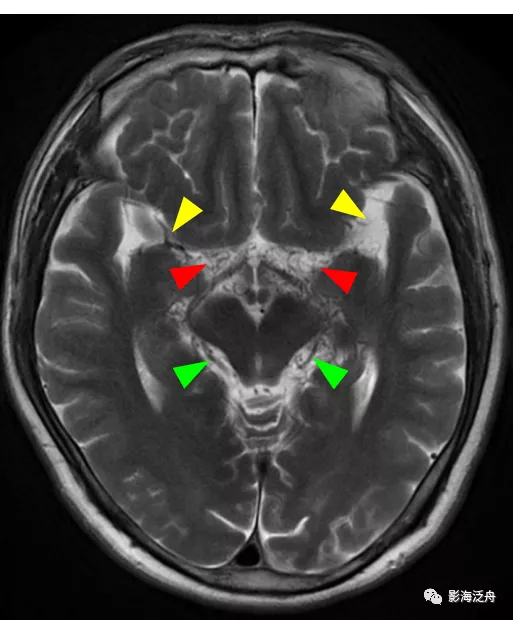

病例一:煙霧病。如圖所示,T2WI序列上在腦底池可以看到多發雜亂的細小流空血管影(紅箭頭),右側側裂池中大腦中動脈間斷顯示,且管腔粗細不均,而左側大腦中動脈完全不顯影(黃箭),兩側的大腦後動脈顯示清晰(綠箭頭)。腦底池中細小血管影增多的另一個常見原因多見於顱內感染,比如病毒性腦炎或隱球菌腦炎等。